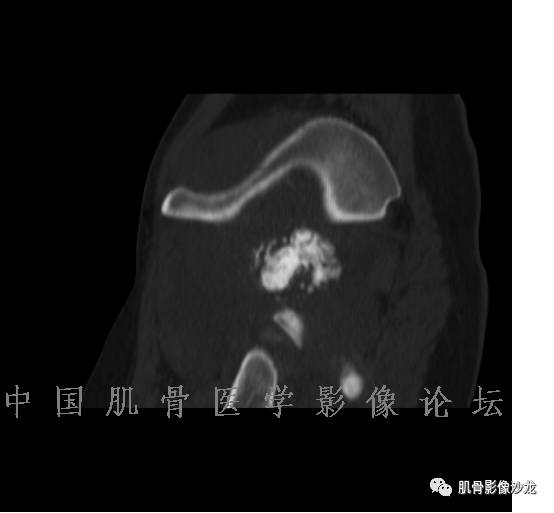

患者2月前无明显诱因下感右腿疼痛、麻木,疼痛呈持续性,发作时无法行走,休息后可缓解。当时无明显肿块,患者遂至当地医院就诊,查X片见右髂骨骨质破坏。6周前患者自觉右髋部渐大肿块,初肿块较小,后肿块逐渐增大,现肿块约12*10cm大小,有压痛。患者遂至我院就诊,查MRI:右髂骨异常信号,伴软组织肿块。ECT、肺CT未见转移。现患者为求进一步治疗,门诊拟“右髂骨肿块 ”收治入院。 患者发病来,神清,精神可,胃纳夜眠可,二便无殊,体重无明显变化。

1、软骨肉瘤可以有膨胀性骨质破坏(病例3,4),可以有溶骨性骨质破坏(病例2),局部皮质因为破坏变薄,中断 ;

2、软骨基质T2WI高信号,软骨小叶分叶状,也就会出现高老师提到的骨内膜扇贝形压迹。一般认为骨内膜扇贝形压迹超过骨皮质厚度的2/3是软骨肉瘤在长管状骨的特征性表现。如上图。3、软组织肿块或肿胀;

4、 钙化,环形,弓形,边缘模糊 ;

5、增强后进行性延迟,不均匀分割状强化, 会强化的纤维间隔,软骨小叶不会强化,关于老师们说到的钙化,软骨肉瘤不一定会有钙化 。